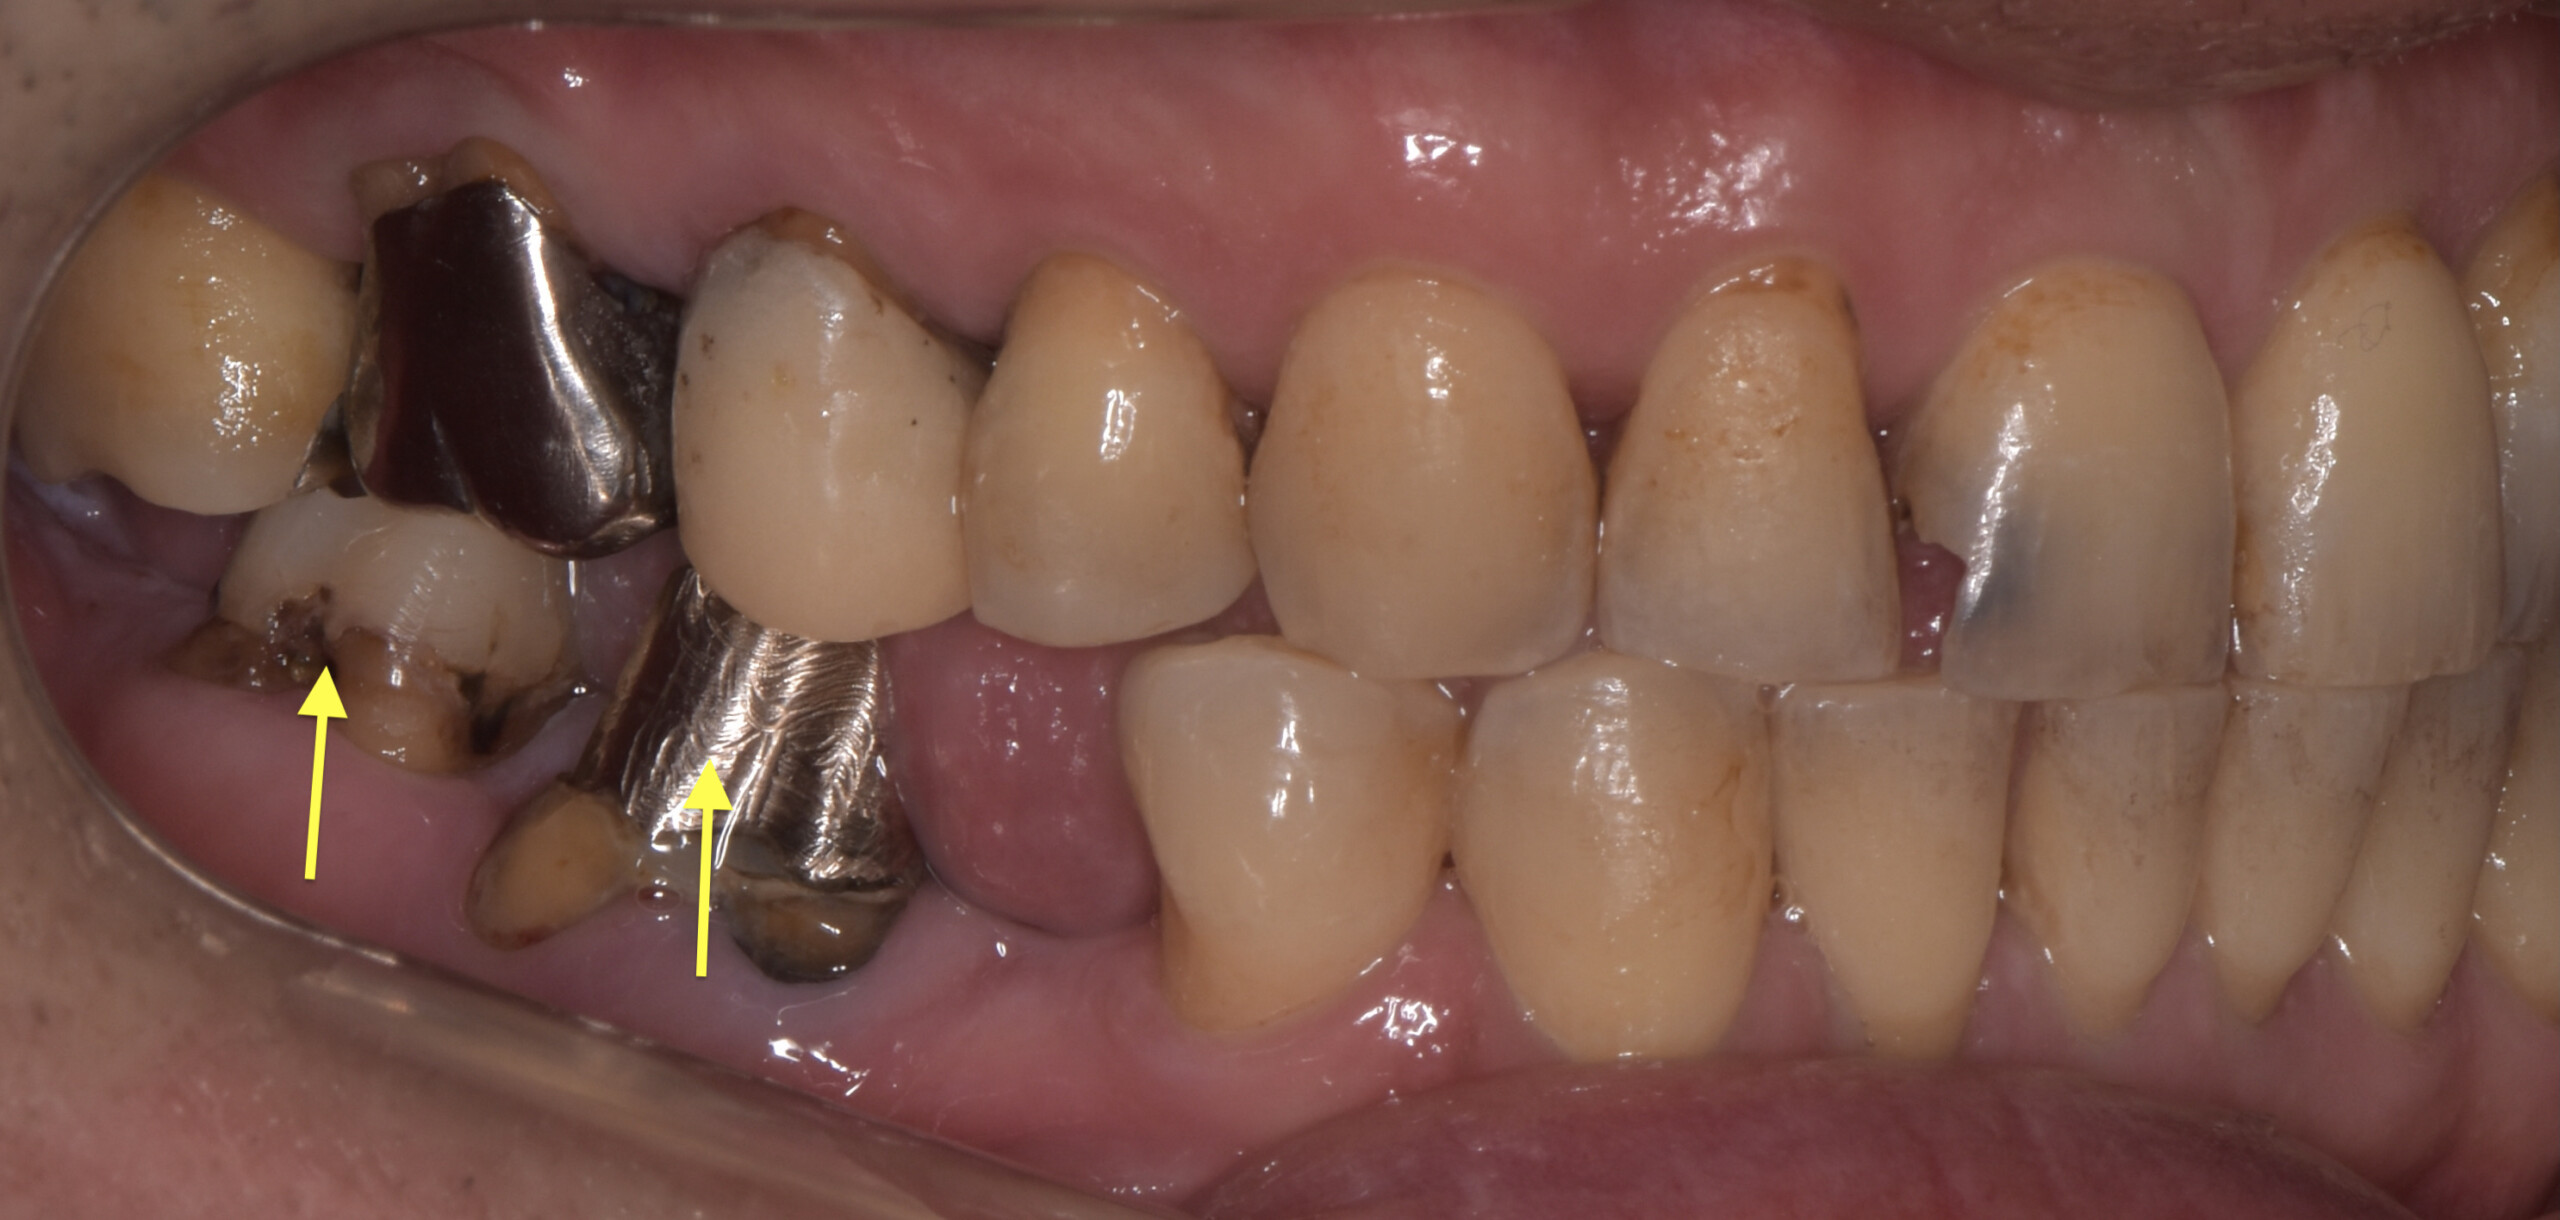

治療前画像の黄色い矢印の歯が非常に強く当たっていることが、デジタルによる画像からもわかります。そこでその歯を抜歯をすることで顎関節の症状が無くなるのではないか?という予測を立てました。

同時にこの歯は大きな虫歯が全く治療されていない事、また破折を起こしていたため結果的に抜歯という選択肢は、虫歯治療という側面からも整合性をもっています。